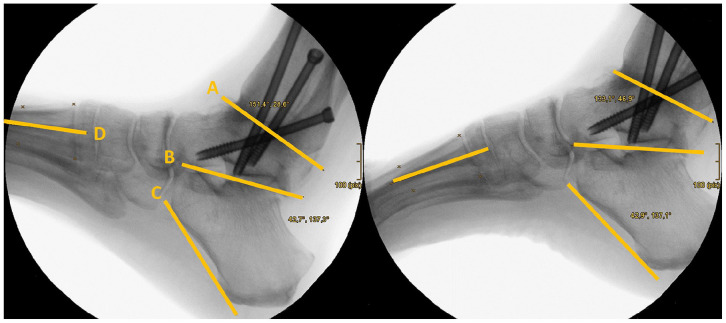

Methods: 29 patients with arthroscopic AAA were analyzed in a retrospective case-control series by pedobarographic gait analysis and fluoroscopy. The variables examined by pedobarography included peak force, peak pressure, and contact time of 10 different zones of the foot during the roll-over process, comparing the operated with the contralateral healthy foot. The range of motion (ROM) of the subtalar and medial tarsal joints in dorsiflexion/plantarflexion were assessed radiologically.

Results: After AAA, peak forces of the ipsilateral foot were significantly reduced for the entire foot and especially the first metatarsal, great toe, and lesser toes during the roll-over process. Peak pressure decreased significantly under the lesser toes and increased under metatarsal 5, without significant load alterations under the mid- and hindfoot. The residual ROM of the subtalar and tarsal joints in dorsiflexion/plantarflexion was 23.5 degrees. The greater the ROM of the adjacent joints, the more the gait pattern normalized.